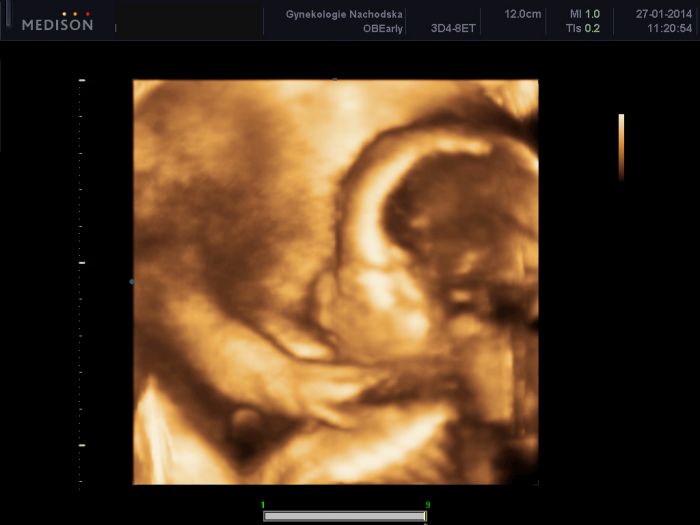

Ahoj holky, mám po kontrole a sláva- vypadá to lépe než posledně. Čípek je stále zkrácený- 230 mm, ale minule mi dr naměřil jen 18 mm. Poctivě jsem ležela a skoro nic nedělala, bříško přestalo tvrdnout a zlepšilo se to!!! Je to obrovská úleva, ikdyž není vyhráno, musím mít dál klidový režim a nic netahat. A jsem doma, ne v nemocnici, to je nejdůležitější. U svojí tříleté lumpice a manžela, ti by mi moc chyběli. Jsem z toho naměkko, ale šťastná. Prcek váží už 660 g a jsem o týden napřed- tedy 23+4.